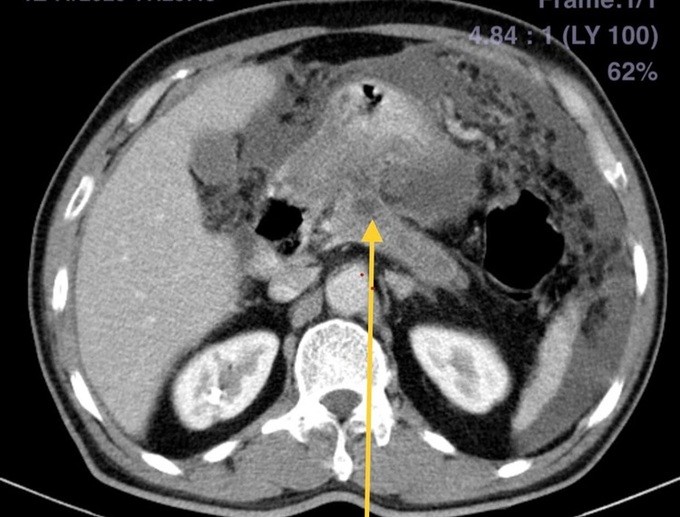

Kỹ thuật diệt hạch bằng cồn tuyệt đối, bệnh nhân không cần gây mê, không mất máu. Dưới hướng dẫn của máy cắt lớp vi tính, bác sĩ đưa chiếc kim nhỏ vào tới vị trí hạch đám rối thân tạng, sau đó tiêm cồn tuyệt đối để diệt hạch. Sau can thiệp, bệnh nhân hết đau, ngủ được, ăn uống trở lại.

Kim tiêm tiến vào đám rối thân tạng dưới hướng dẫn của hình ảnh cắt lớp vi tính. Ảnh:Bệnh viện cung cấp

Thực hiện kỹ thuật cần có hướng dẫn của các phương tiện chẩn đoán hình ảnh như siêu âm, cắt lớp vi tính, màn tăng sáng. Đường kim chọc vào đám rối thân tạng phải chính xác tuyệt đối, tránh làm tổn thương các tạng trong ổ bụng hoặc mạch máu khi can thiệp.